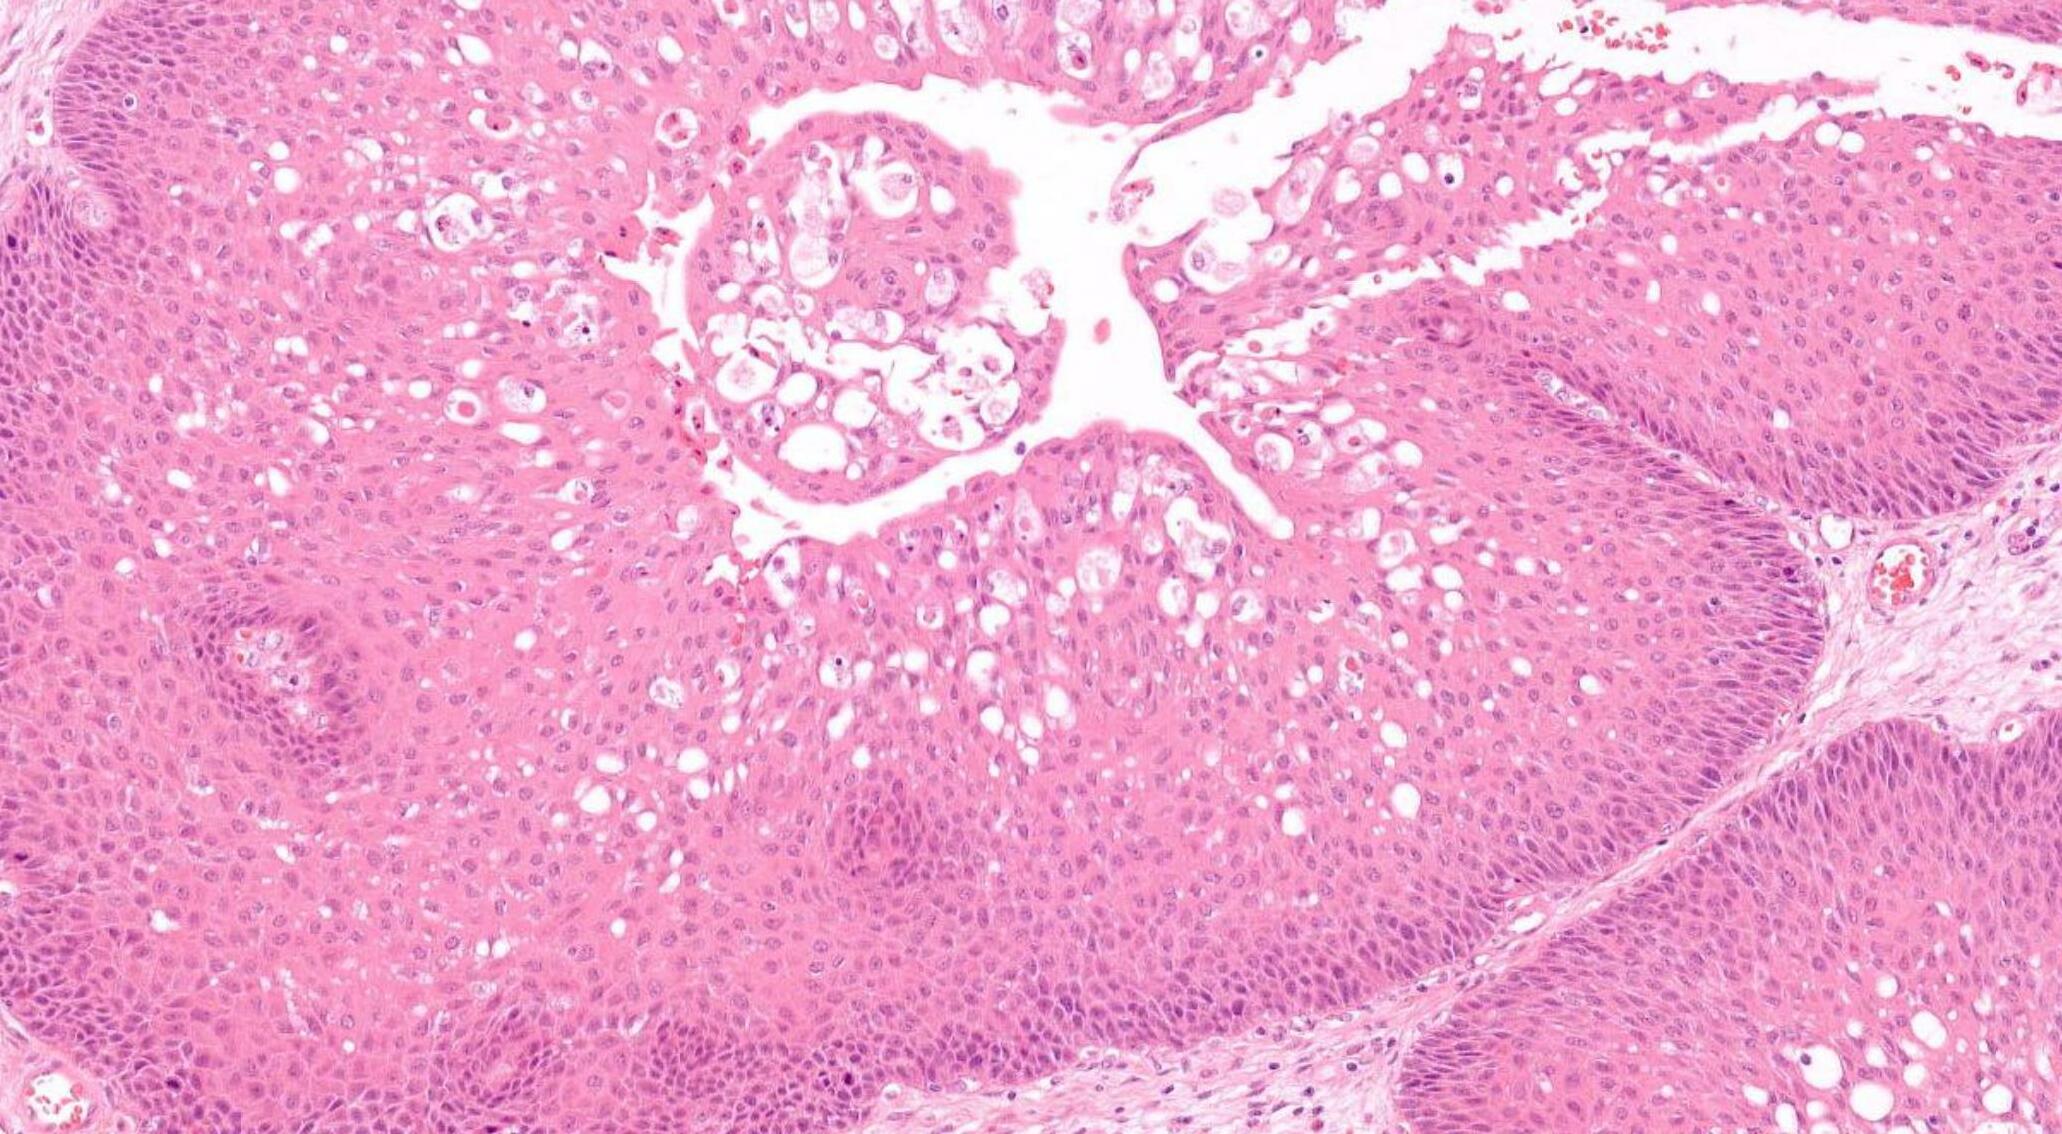

Case 1- Salient points • Circumscribed salivary tumour, infiltrative periphery • Papillary cystic, microcystic patterns, hobnailing • Solid sheets of large polygonal cells with granular eosinophilic cytoplasm and vesicular nuclei • Secretory material –colloid-like eosinophilic secretions • Occasional mitotic figures • Work up? PAS, DPAS, • CK7, S100, DOG1, Mammoglobin

Secretory carcinoma

Discussion Differential diagnoses • Acinic cell carcinoma • Secretory carcinoma (previously called MASC) • MEC • 90% -ETV6::NTRK3 fusion -chromosomal rearrangement, t(12;15) (p13;q25) • ETV6::RET, ETV6::MET, ETV6::MAML3 • ETV6 translocation-negative secretory carcinoma. • Similar to Acinic cell carcinoma • But S100+, Mammoglobin+, DOG1-

5th ed Essential and desirable diagnostic criteria • Essential: single cell type with vacuolated colloid-like secretory material; no zymogen cytoplasmic granules; IHC positivity for S100 protein, SOX10, and mammaglobin; lack of IHC staining for p40 and/or p63 • Desirable: ETV6 or RET rearrangement demonstrated by FISH, RNA sequencing, or PCR • Low grade • Lymph node metastases are reported in as many as 25% of cases